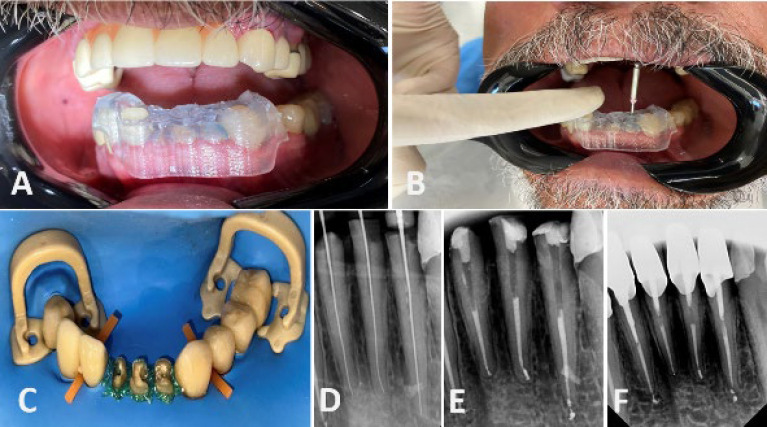

美国牙髓学协会将髓管闭塞(PCO)病例的处理列为高风险困难。这种分类表明程序错误的可能性增加了。然而,牙科技术的进步简化了钙化牙齿的牙髓治疗。引导牙髓学使用锥形束计算机断层扫描(CBCT)和三维(3D)打印机来创建针对患者的指南,提高了复杂病例的准确性和可预测性。一名健康的60岁男性由一名修复医生转介对23号、24号和25号牙齿进行根管治疗。根尖周x线检查显示所有牙齿均有部分PCO。选择牙髓治疗后,利用CBCT成像和口腔内3D扫描设计患者特异性牙髓治疗指南。在验证了内导器的稳定性后,使用Munce Discovery钻头制备了通道腔。在运河协商之后,确定了工作长度。根管治疗使用25/0.04%旋转锉和次氯酸钠冲洗。采用热冷凝技术完成封闭。虽然PCO存在,但治疗过程中未发生并发症。牙齿保持完全无症状和功能,表明治疗成功。引导牙髓治疗是治疗下颌骨PCO的一种实用且可预测的方法。该技术提供了准确的根管定位,减少了程序错误,并保留了牙齿结构。尽管担心成本、辐射暴露和解剖学变异的挑战,但它代表了根管治疗的一个有希望的进步。

The American Association of Endodontics classifies the management of pulp canal obliteration (PCO) cases as a high-risk difficulty. This classification indicates an increased likelihood of procedural errors. However, advancements in dental technology have simplified the endodontic treatment of calcified teeth. Guided endodontics uses cone-beam computed tomography (CBCT) and a three-dimensional (3D) printer to create a patient-specific guide, enhancing accuracy and predictability in complex cases. A healthy 60-year-old male was referred by a prosthodontist for root canal treatment on teeth #23, #24, and #25. Periapical radiographic examination revealed partial PCO in all teeth. After choosing guided endodontics treatment, CBCT imaging and intraoral 3D scanning were utilized to design a patient-specific endodontic guide. After verifying the stability of the endo-guide, access cavities were prepared using a Munce Discovery bur. Following the negotiation of the canals, the working length was determined. Root canal treatment was performed using rotary files up to size 25/0.04% and sodium hypochlorite irrigation. The obturation was completed using the warm condensation technique. Although PCO was present, no complications occurred during treatment. The teeth remained completely asymptomatic and functional, demonstrating the success of the treatment. Guided endodontics can be a practical and predictable approach for managing PCO in mandibular incisors. This technique provides accurate canal location, reduces procedural errors, and preserves tooth structure. Despite concerns about cost, radiation exposure, and challenges with anatomical variations, it represents a promising advancement in endodontic treatment.